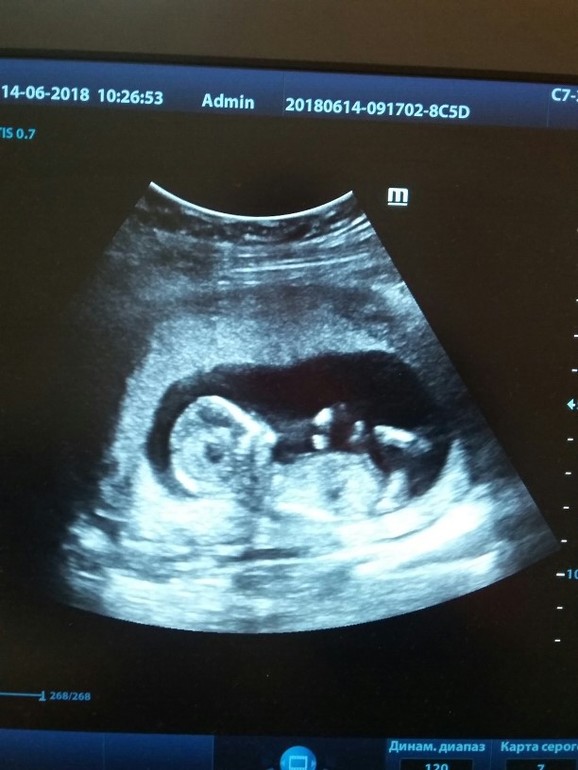

УЗИ, КТГ, доплерЯ сегодня ходила на наш первый скрининг. Думала не доживу до него. Все таки страхи после зб меня не покидали. Но когда сегодня включили сердечко....... чуть не расплакалась от счастья. Все у нас в норме. Развиваемся отлично. Все в срок.

К слову в кабинете узи я была 4 минуты)))) Ага ага. вот она бесплатная медицина. Но я все равно благодарна врачу, она все спкойно сама и понятно мне все расказывла. В конце дала сфотографировать на телефон нашу лялю.... Как я уже его сильно люблю. Прям нет сло. Мой день сегодня сделан... И сделан самым лучшим образом. Всем любви, добра и счастья. И наша крошечка на память мне в дневничек

Сейчас 13 по узи. Примерно так и по м.